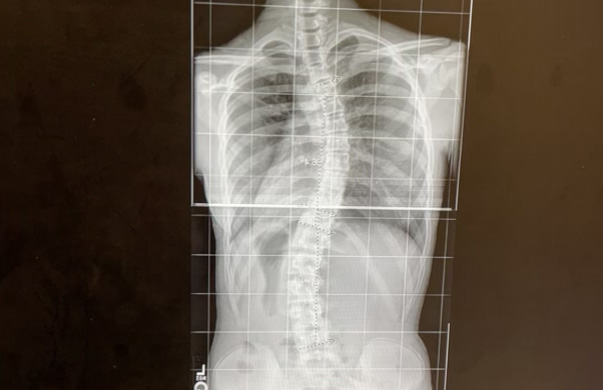

I remember standing in front of my mirror that night. I could see the unevenness in my shoulders that I’d always brushed off as nothing more than the result of bad posture. But then, I had my parents look at my back, and they instantly saw the “S” curvature on my spine.

A month later, my doctor confirmed my worst fears. “Taylor, you have moderate scoliosis.” That term, scoliosis, a term I’d only just learned from a random TikTok video, had suddenly become an intrinsic part of my life. The wrestling mat, once my sanctuary, now seemed daunting. Every hold and throw reminded me of the curve in my spine. But I wasn’t going to let scoliosis hold me down.